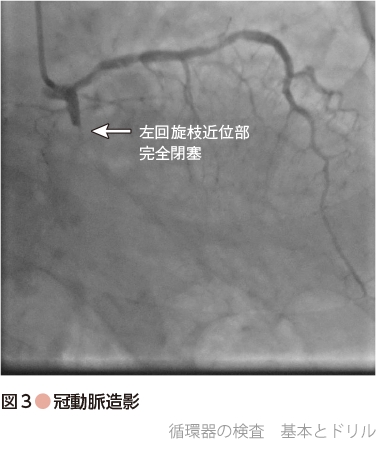

心臓カテーテル検査を施行したところ,左回旋枝領域が近位部で完全閉塞の所見を認めた(図3).よって,今回の胸痛の原因,また心原性ショックの原因は左回旋枝領域の急性心筋梗塞と診断.血圧低下も遷延していたため,昇圧薬サポートを行い,同部位に対してPCIを行った.最終的に完全閉塞部位に対して薬剤溶出性ステントを1本留置し,手技終了.その後,胸痛症状も改善,バイタルサインも改善.血圧は180 mmHg程度まで上昇したため,昇圧薬使用も中止とした.